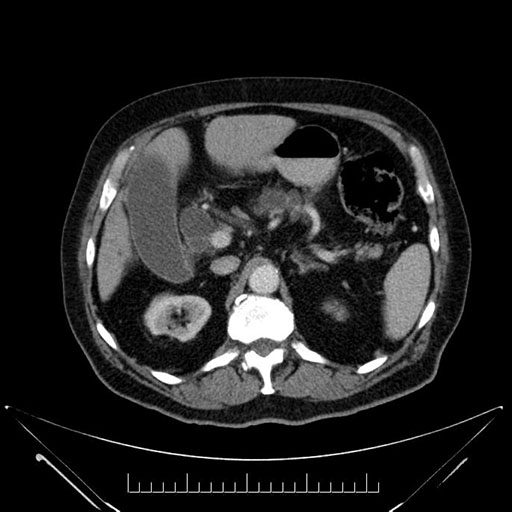

Axial - 3 months prior